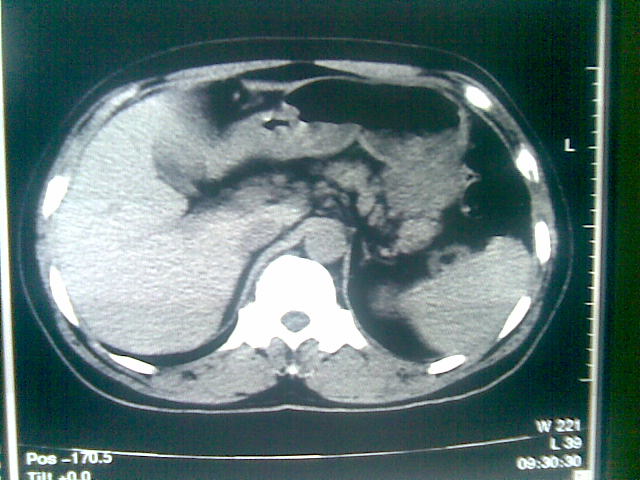

标题: CT23981:男,38岁阑尾炎术后透视胸腔积夜!做CT如下!积液包 [打印本页]

标题: CT23981:男,38岁阑尾炎术后透视胸腔积夜!做CT如下!积液包

可能与阑尾术后关系不太大,1.胸膜增厚粘连见少量气体。包裹脓气胸?左侧网膜囊脓肿?

.胸膜增厚粘连见少量气体。包裹脓气胸

少量积液部分粘连

左侧胸膜增厚、粘连+包裹液气胸。